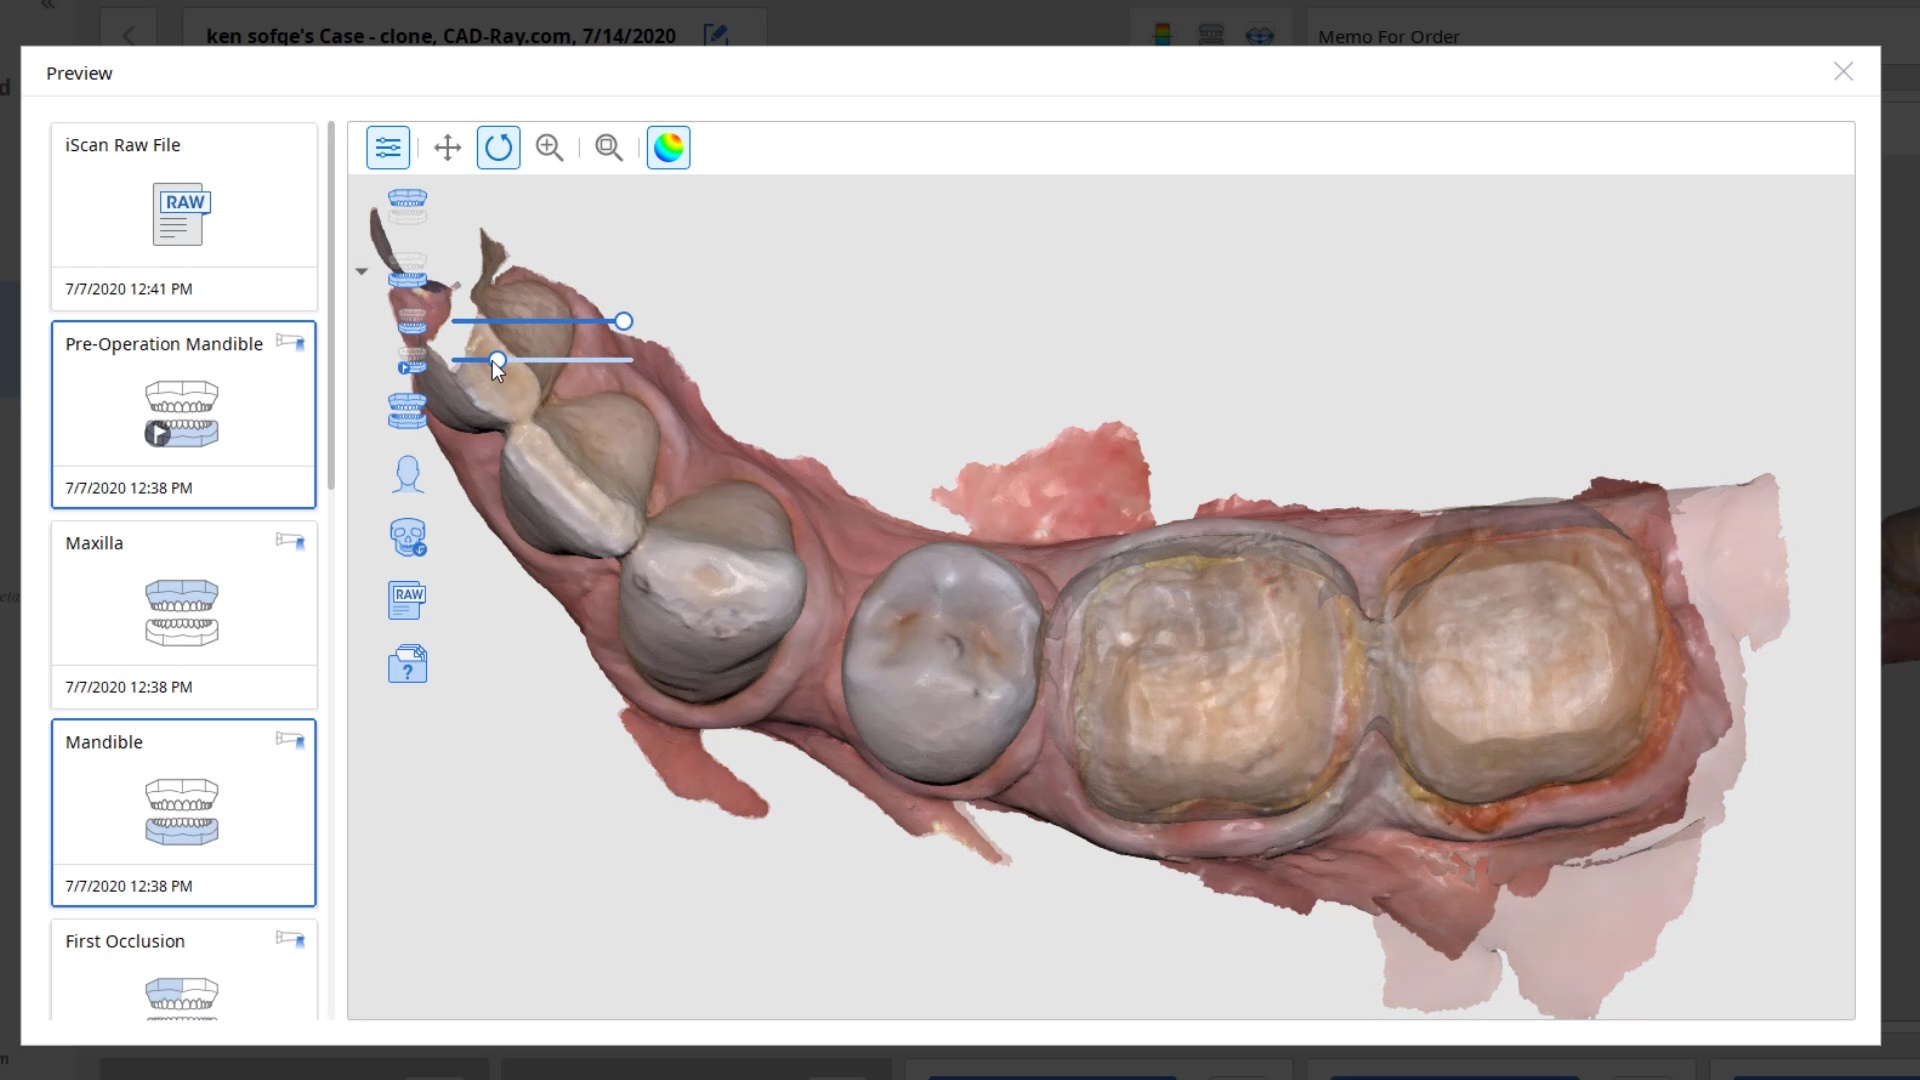

For our advanced users who mill in house or what to speed up their digital impressions we advocate taking advantage of digital dentistry’s unique features that allow you to take impressions over a period of time and segments, building larger models over different sequences and time. In this particular case we have two molars in the lower left quadrant that warranted replacement. The traditional method would be to prep both, isolate both, retract both, and take your final impression, but we will approach this as if there are two separate patients involved

For the second molar, we will take advantage of the anesthesia time and capture the first bite, the opposing, the pre-existing situation and then crop out the preparation area digitally. Once the tooth is prepared, we will check for proper reduction. We will then take the second bite to verify the vertical dimension has not changed.

While the second molar is being designed and milled in the first case, we will launch a second window by cloning the first case. All the data remains the same and this time we crop out the first molar digitally and protect the rest of the arch. Once the first molar is isolated, it is digitally captured and then designed and milled.

To manage the contact between the two crowns, there are many advanced applications. Here is a simple explanation of how we use the prep model from case 1 as the pre-op model for case two. Since the second molar in case 1 made contact with the distal wall of the first molar, when we design the crown for the first molar in case 2, all we have to do is make sure the distal wall is flush to the pre-op. This guarantees us a contact between the two. There are lots of shortcuts to this puzzle once you get the basics of digital impressions under your belt.